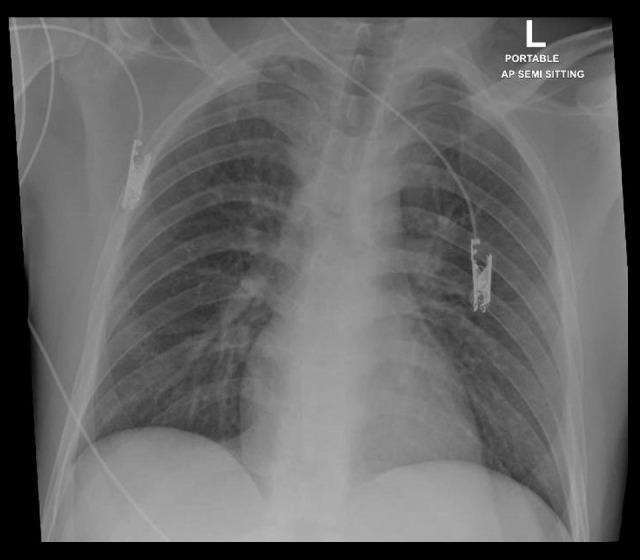

BACKGROUND Coronavirus disease 2019 (COVID-19) is a newly emerging disease that is still not fully characterized. It is caused by severe acute respiratory syndrome coronavirus 2 (SARS-CoV-2), a novel virus that can be transmitted easily from human to human mainly by the respiratory route. Currently, there is no specific treatment for COVID-19 or a vaccine for prevention. The disease has various degrees of severity. It often presents with nonspecific symptoms such as fever, headache, and fatigue, accompanied by respiratory symptoms (e.g., cough and dyspnea) and other systemic involvement. Severe disease is associated with hemophagocytic syndrome and cytokine storm due to altered immune response. Patients with severe disease are more likely to have increased liver enzymes. The disease can affect the liver through various mechanisms. CASE REPORT We report an unusual case of SARS-CoV-2 infection in a 24-year-old man with no previous medical illness, who presented with mild respiratory involvement. He had no serious lung injury during the disease course. However, he experienced acute fulminant hepatitis B infection and cytokine release syndrome that led to multiorgan failure and death. CONCLUSIONS It is uncommon for SARS-CoV-2 infection with mild respiratory symptoms to result in severe systemic disease and organ failure. We report an unusual case of acute hepatitis B infection with concomitant SARS-CoV-2 leading to fulminant hepatitis, multiorgan failure, and death.

背景 2019 冠状病毒病(COVID-19)是一种新出现的疾病,目前仍未完全明确其特征。它由严重急性呼吸综合征冠状病毒 2(SARS-CoV-2)引起,这是一种新型病毒,主要通过呼吸道途径在人与人之间容易传播。目前,尚无针对 COVID-19 的特效治疗方法或预防疫苗。该疾病有不同程度的严重程度。它常表现为发热、头痛和疲劳等非特异性症状,伴有呼吸道症状(如咳嗽和呼吸困难)以及其他全身受累表现。重症疾病与免疫反应改变导致的噬血细胞综合征和细胞因子风暴有关。重症患者更易出现肝酶升高。该疾病可通过多种机制影响肝脏。病例报告 我们报告一例非同寻常的 SARS-CoV-2 感染病例,患者为一名 24 岁既往无病史男性,表现为轻度呼吸道受累。在病程中他没有严重的肺损伤。然而,他经历了急性暴发性乙型肝炎感染和细胞因子释放综合征,导致多器官功能衰竭和死亡。结论 伴有轻度呼吸道症状的 SARS-CoV-2 感染导致严重全身疾病和器官衰竭的情况并不常见。我们报告了一例非同寻常的急性乙型肝炎感染合并 SARS-CoV-2 导致暴发性肝炎、多器官功能衰竭和死亡的病例。